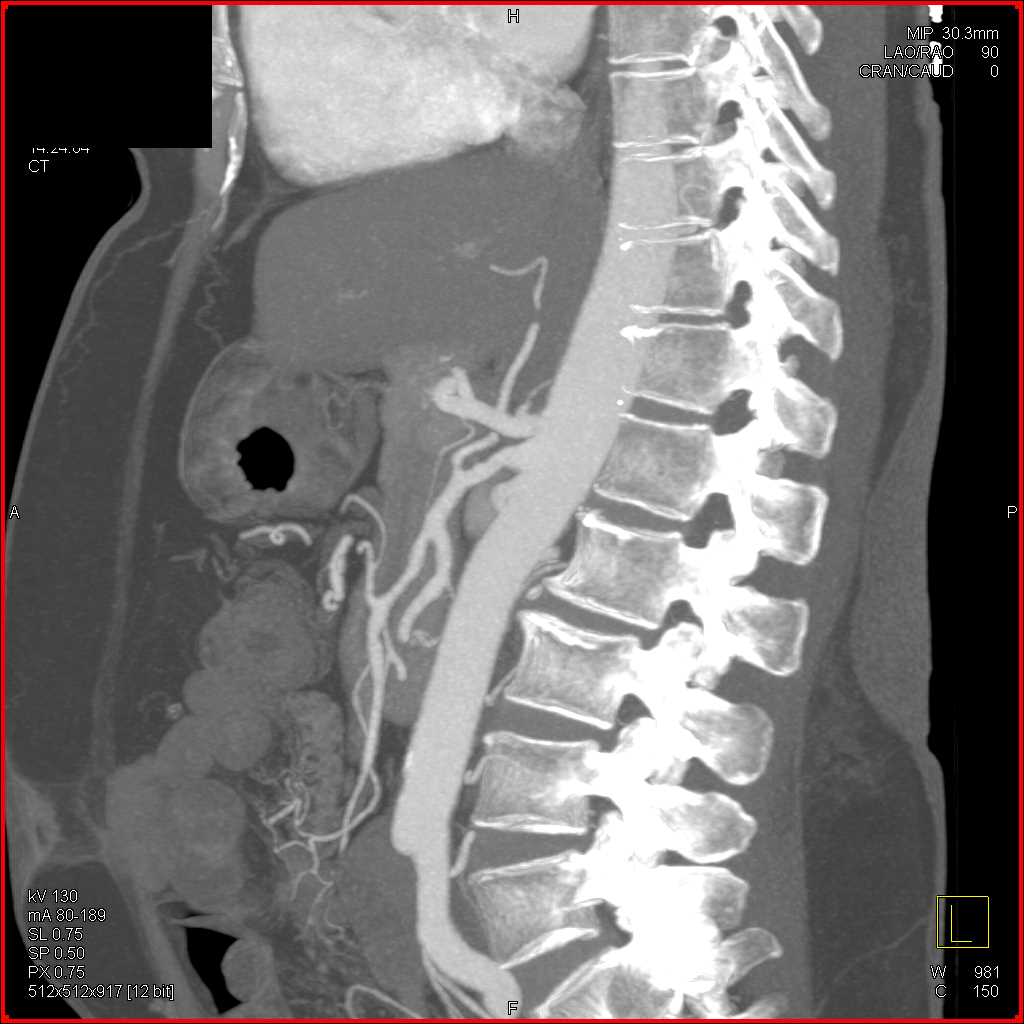

Neuroendocrine Tumor Body of Pancreas